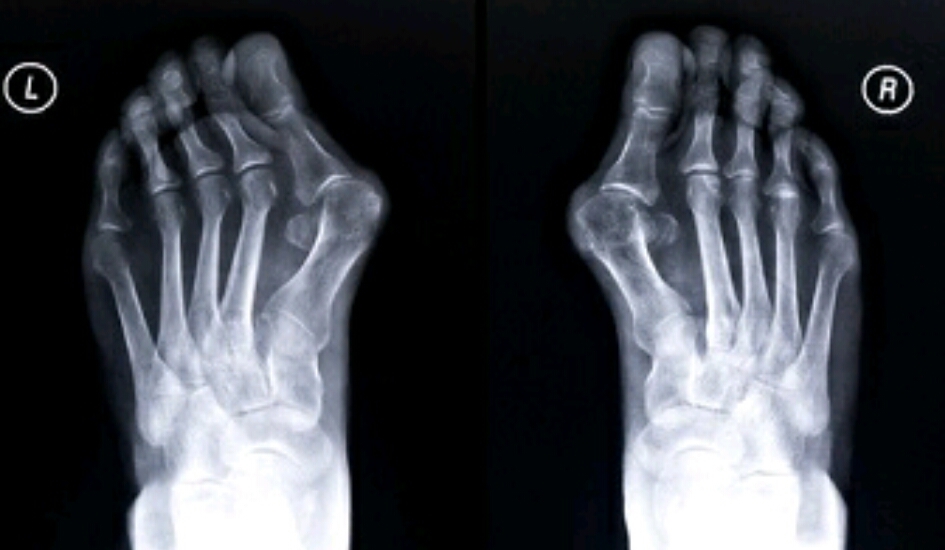

Name the feature. What disease does this represent?

hallux valgus

DJD

Name the feature. What disease is this associated with?

metatarsus varus

Name the feature. What disease does this correlate with?

(Inflammation, pain)

bunion